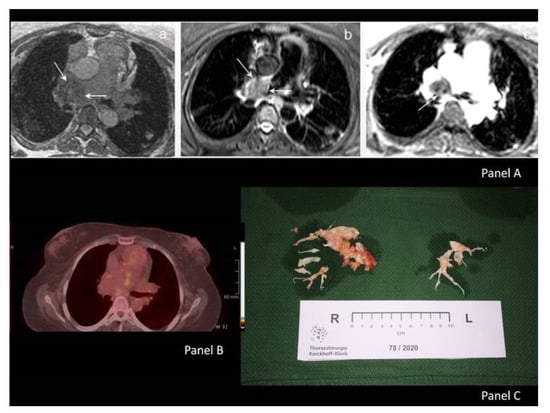

Giant Pulmonary Artery Thrombotic Material, Due to Chronic Thromboembolic Pulmonary Hypertension, Mimics Pulmonary Artery Sarcoma